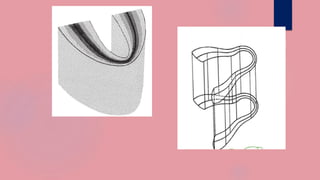

WIDTH/THICKNESS OF THE FOCAL PLANE

The thickness of the focal plane is determined by the

amount of movement, or angle of swing, of the

equipment.

The larger the angle of swing, the thinner the section in

focus, while the smaller the angle of swing the thicker the

section.